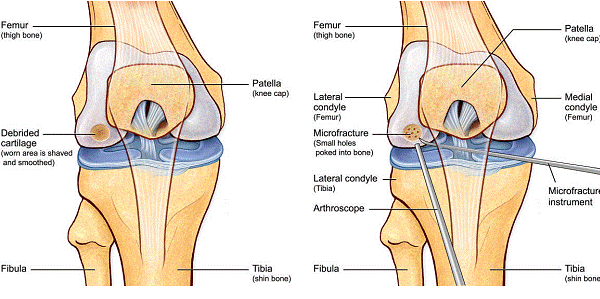

Chirurgul trebuie sa fie foarte atent atunci cand examineaza posteriorul condililor femurali. Daca se semnaleaza orice vatamare/rana/deteriorare pe suprafetele articulare, trebuie sa se cerceteze atent calitatea cartilajului. Orice flapsuri instabile sunt inlaturate prin folosirea unui aparat de ras electric artroscopic sau curette. Apoi, un curette este folosit pentru a debrida stratul de cartilagiu calcifiat de la baza in toata grosimea defectului. Acest pas se bazeaza pe activitatea lui Frisbi, care a demonstrat vindecarea suprafetei articulare superioare la un cal, cand stratul cartilagiului calcifiat este indepartat. Cand indepartam stratul cartilajului calcifiat, in general nu se foloseste un aparat de ras. Cu un aparat de ras este dificil de controlat cantitatea de os eliminat, si este posibil ca osul subcondral sa fie afectat.

Dupa indepartarea cu succes a stratului de cartilaj calcifiat, o andrea este folosita pentru a face mai multe gauri mici (mirofracturi) in osul expus al defectului condral aflate la distanta de 1-2 mm. Trebuie lasata o punte de oase potrivita intre gauri. Tehnica de microfracturi are numeroase avantaje fata de foraj. Mai intai de toate, creaza o leziune termala mai mica. Mai mult, cu microfracturi chirurgul este capabil sa intre in zonele dificile ale suprafetei articulare cu un control mai bun asupra adancimii de patrundere. La finalizarea microfracturii, o suprafata aspra este generata pentru aderenta cheagului de sange care contine celule mezenchimale nediferentiate de la osul subcondral. Trebuie avut grija ca cele mai marginase parti ale leziuni sa fie patrunse de andrea pentru a ajuta la vindecarea tesutului reparator la imprejmuirea suprafetei articulare. Odata ce microfractura este finalizata, pompa artroscopica este oprita pentru a se asigura ca sangerarea maduvei curge din gaurile mici umpland defectul.[54]

Fig.23. Diagrama microfracturi: a. Leziunea; b. Rezultatul interventiei.

Andrelele de microfracturare cu unghi reglat actioneaza moderat astfel incat gaurile verticale pot fi facute fara daune termice. Se fac gauri chiar de la marginea defectului.

Fig.24. Diagrama interventiei chirurgicale.

Fig.25.a. Debridarea. Fig.25.b. Microfracturare.

Fig.26. Diagrama unei microfracturari.